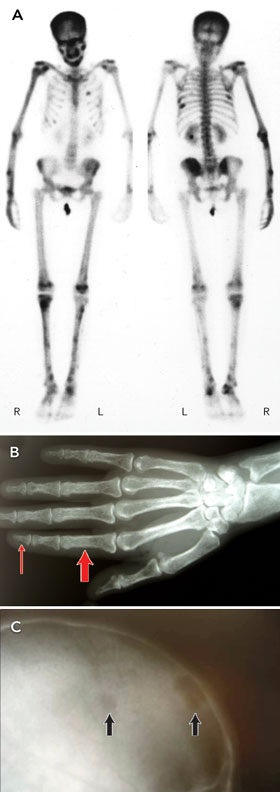

Primary hyperparathyroidism (PHT) complicated by osteitis fibrosa cystica (OFC) — the “classical” form of PHT — is rarely seen today. A 41-year-old woman of Sri Lankan descent presented with persistent pain in her right distal forearm 2 days after chopping vegetables. X-ray revealed a fracture through a lucent lesion within the midshaft of the right ulna. A whole-body bone scan showed numerous abnormalities of the major long bones consistent with OFC (Figure, A). Skeletal x-rays showed widespread lytic lesions with osteopenia and subperiosteal erosions, illustrated here by x-ray of the right hand (Figure, B) where marked subperiosteal bone resorption can be seen; note the ill-defined phalangeal cortex (thick arrow) and erosion of the terminal tufts of the distal phalanges (thin arrow). Skull x-ray showed “salt-and-pepper” demineralisation (Figure, C), best appreciated by the lack of visible vascular markings on the calvarium; lytic lesions are present (arrows). The serum calcium level was 4.22 mmol/L (reference range, 2.13–2.63 mmol/L). Our patient was successfully treated with a parathyroidectomy — 5 months after surgery, bone turnover markers were normal, and 14 months after surgery, bone mineral density, tested at the hip, had increased by 22%.